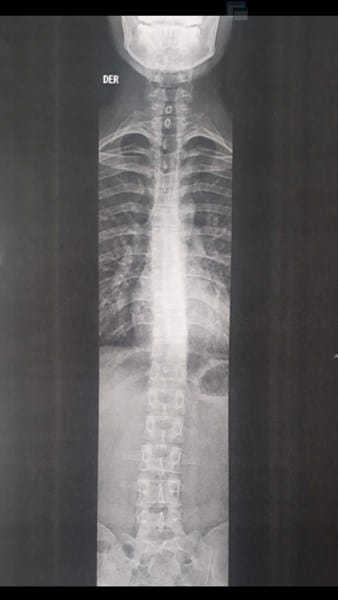

¿Cuantos grados de escoliosis tengo.? RX columna vertebral.

Me hice una radiografía de columna vertebral total. Pero no e conseguido que nadie me diga cuantos grados tengo de escoliosis. Unos me dicen que es de TIPO C y otros TIPO S pero en si no me dicen los grados. Me urge saber porque pienso presentarme a las FM. Y hay piden que sea menor de 7 grados de escoliosis. ( En el dictamen de la radiografía dice que no tengo nada. Pero se evidencia que tengo una desviación normal)